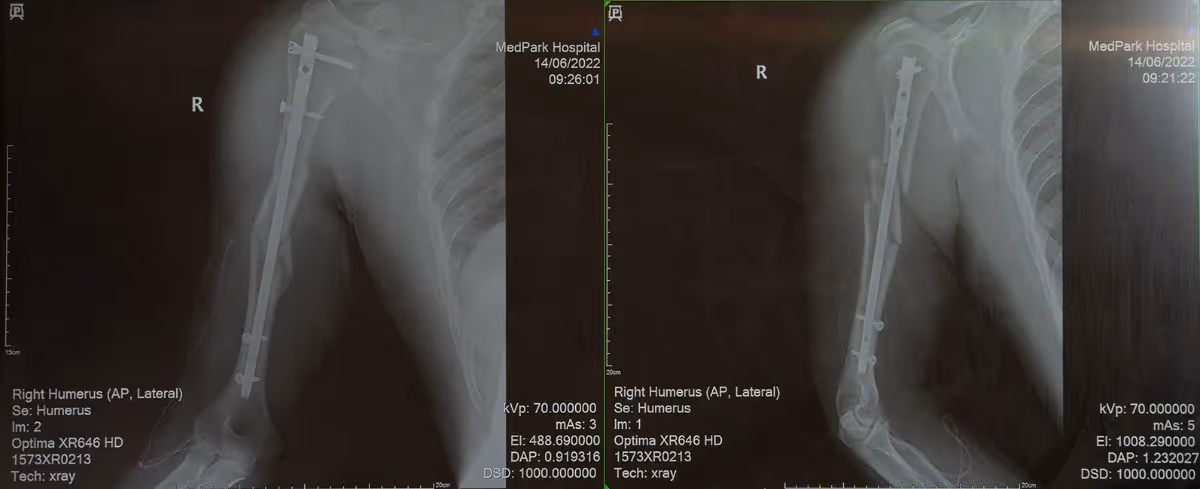

Right Humerus 2

Ryan required six surgeries, including a neurosurgery due to intracerebral hemorrhage. These were trying times demanding willpower, patience, and discipline. Following the surgeries came rehabilitation and physical therapy.

“I can move my fingertips, just barely. But when I attempted to grab something, my hand would curl in and droop. The doctor advised me to persist in daily practice to stimulate my nerves. It was quite challenging for me. My arm atrophied as the muscle mass was thinning, but Dr. Jay reminded me that I needed to overcome this and said he knew I could. He estimated my best recovery would be about 80%, but I was determined to go for 100%.”

Right Humerus

“He had four fractures, one of the right clavicle, treated at the first hospital with open reduction and internal fixation. The other three were on his right arm, treated with an external fixator frame. In addition, he had a palm-length wound over his ribs. He could not flex his right wrist back, probably due to nerve damage in his right arm. Plus, he had intracerebral hemorrhage. The injuries spread throughout his entire body.”

In the past, external fixation was usual because of its convenience and simplicity -- small metal pins are inserted through the skin and drilled into the bone fragments above and below the fracture site. An external frame may hinder sleep and movement of the affected arm. In Ryan's case, the referring hospital performed external fixation as a stop-gap measure; it is not as strong as internal fixation. Another disadvantage is the possibility of nonunion. Because of this, Dr. Pongsakorn decided to reoperate for fracture repair.

“For open fixation with plate and screws, the wound will be 15-20 centimeters long. We planned to place a metal rod into the central medullary cavity of the bone. The rod is called an intramedullary nail. An X-ray imaging with fluoroscopy was required to guide the nail placement. We made a small incision near the end of the bone and drilled into the medullary cavity to insert the nail.  The small incision allowed for quick recovery.”

The outcome was satisfactory to a large extent. Dr. Pongsakorn said most broken bones heal within 2-3 months. And for nerves, it takes about 3-6 months. Some people only recover 30% to 50% of their normal nerve function, while Ryan achieved almost 100% recovery. For his right clavicle, the team of physicians reached a consensus that revision surgery was necessary to bring the fixation plate closer to his clavicle.

“His bones fully mended in two months, and it required approximately three months for his nerves and chest injury to heal before resuming work, just in time to greet his new baby. Ryan deserves recognition for his unwavering resolve. He had foreseen a complete recovery, and I am pleased that he has admirably attained this degree of recovery.”